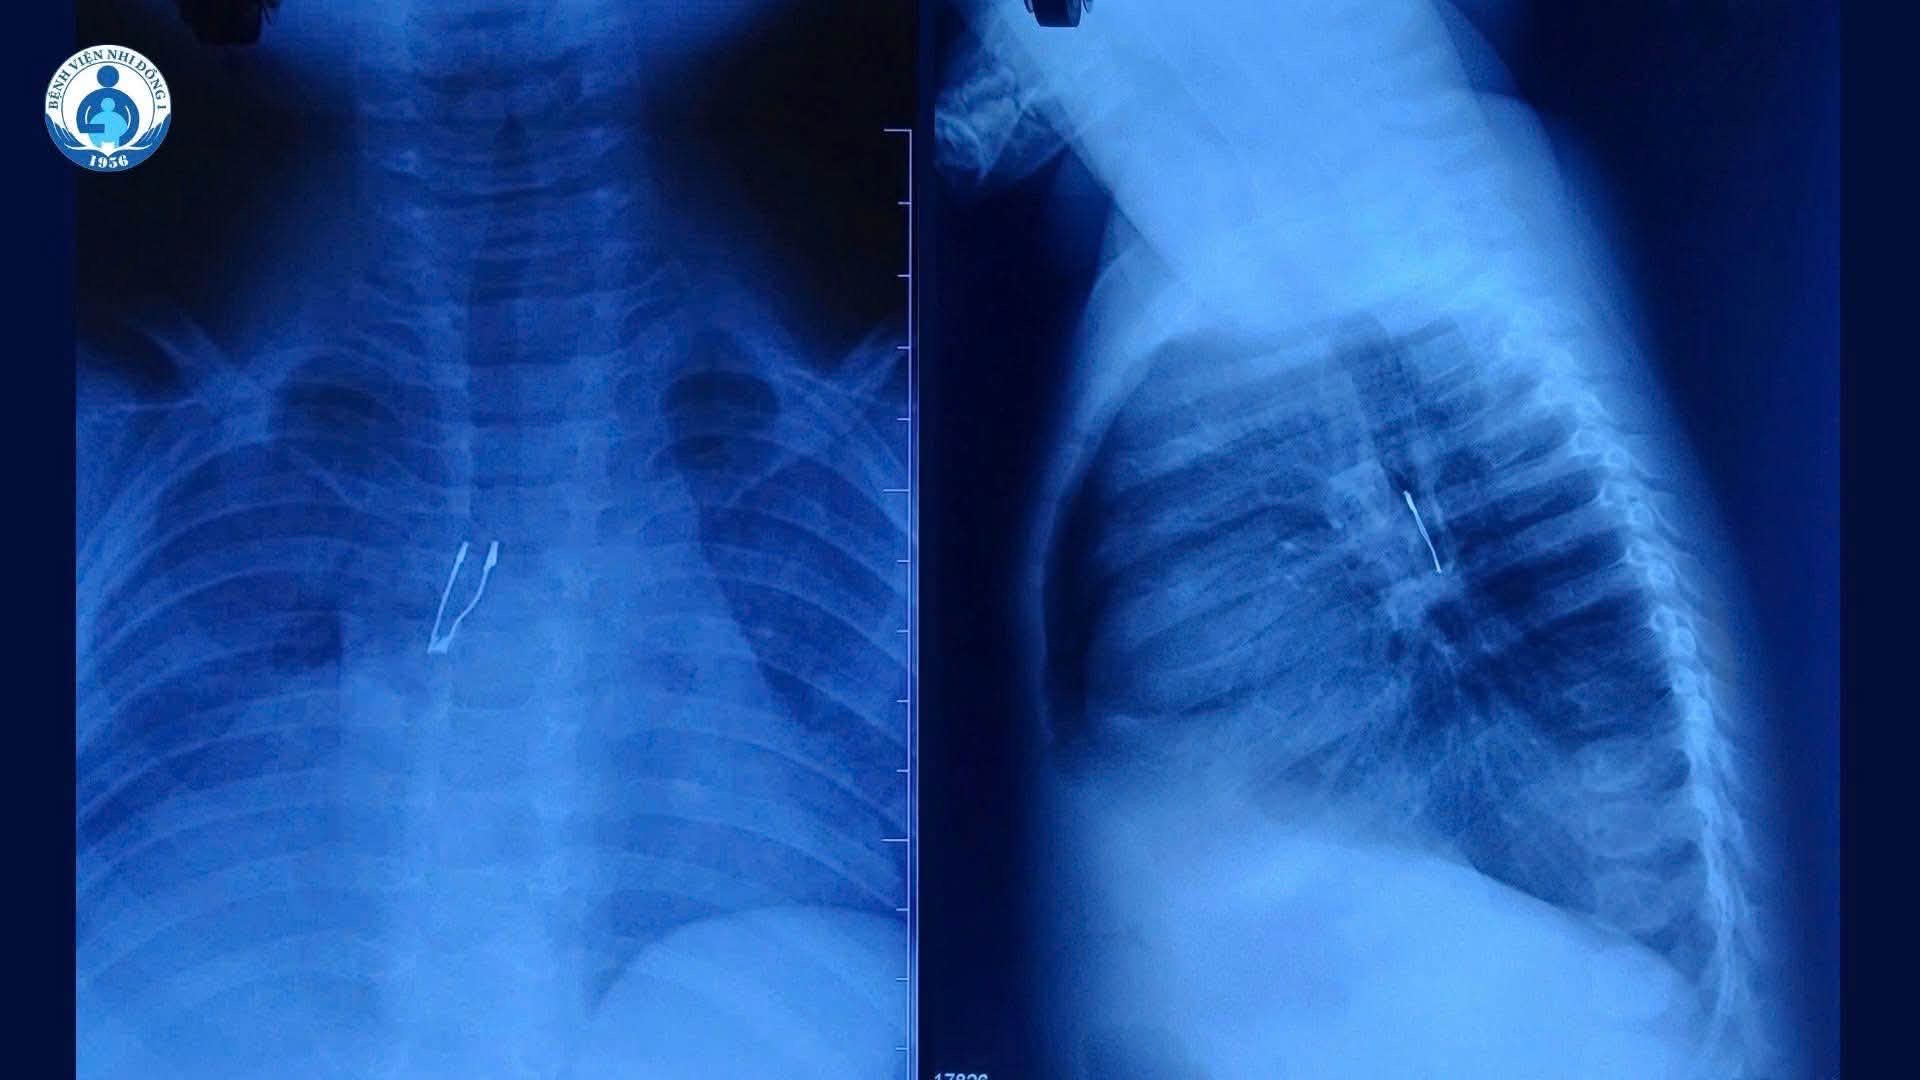

Hình ảnh X-quang cho thấy dị vật nằm ở phế quản gốc phải bệnh nhi

Bệnh nhi N.K.N (9 tháng tuổi, ở Đồng Tháp) nhập viện trong tình trạng ho kéo dài hai ngày. Trước đó, tại tuyến y tế ban đầu, hình ảnh X-quang ghi nhận dấu hiệu bất thường nghi ngờ dị vật đường thở nên trẻ được chuyển đến Bệnh viện Nhi Đồng 1 để tiếp tục xử trí. Gia đình không xác định được thời điểm trẻ hít phải dị vật cũng như loại dị vật cụ thể.

Tại bệnh viện, kết quả chẩn đoán cho thấy dị vật cản quang nằm ở phế quản gốc phải, kèm theo tình trạng xẹp phổi phải không hoàn toàn và tràn khí trung thất.